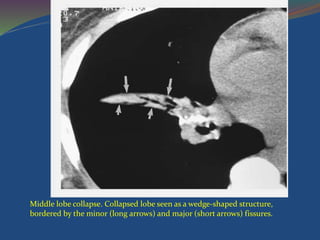

Middle lobe collapse. Collapsed lobe seen as a wedge-shaped structure,

bordered by the minor (long arrows) and major (short arrows) fissures.